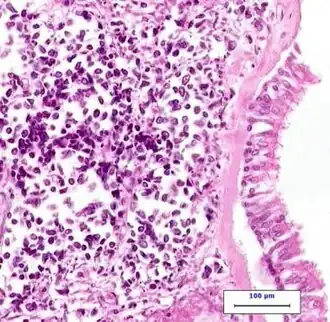

Though results of imaging test might be suggestive of lung cancer, the actual diagnosis is made by investigating the lung cells under the microscope via lab tests. The cells can be obtained from lung secretions (sputum cytology), fluid removed from pleural effusion (thoracentesis), or from a suspicious area (needle biopsy).[15]